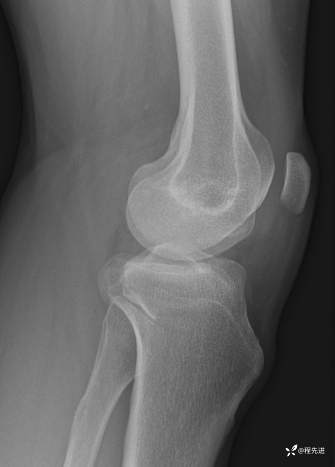

右肘关节正侧位DR:

img